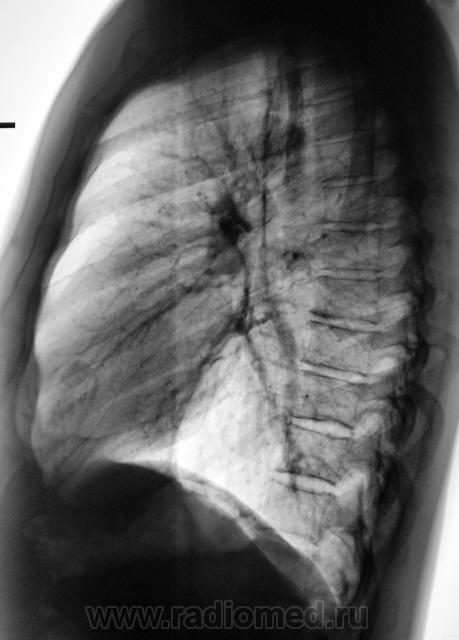

Слева в S6 (если не ошибаюсь) похоже на перифирический. На боковой накладывается кальцинат в л/у корня.

Если диагноз туберкулёмы слева подтвердят, то тень в S5 справа следует отнести к туберкулёме. С уважением Nikolas

Мы, благодаря "Сиару" увеличили и обработали эту тенюху, и вот что получили.

Мы долго колебались между диагнозами периферического рака и туберкуломы, остановились на "периферическом", пациент был направлен в областную онкологическую "контору", где и был прооперирован.

Вы оказались правы уважаемый коллега. На операции, с последующей верификацией оказалась туберкулома.